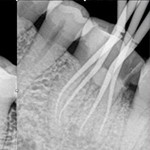

牙齒根管治療就是我們俗稱的堵牙,通過治療,保留患牙。具體就是對牙齒,牙髓,根尖病變的一個(gè)治療過程,通過清楚根管內(nèi)的壞死物質(zhì),適當(dāng)?shù)南?,填充牙齒根管,防止根尖周病變的一種治療方法。

效果展示

根管治療 根管治療 根管治療 根管治療

5.為了保證療效,通常應(yīng)在治療的前、中、后拍攝多張牙片,以確保根管通暢和充填到位